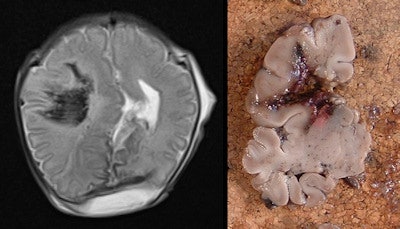

Example of intracranial hemorrhage. Axial T2-weighted postmortem MRI demonstrates right frontoparietal parenchymal hemorrhage in a 35-week gestation, fetal stillbirth (left), confirmed on histology (right). All images courtesy of Dr. Owen Arthurs.Studies such as this are changing the way autopsies are performed and helping to develop the concept of less-invasive autopsy, according to lead study author Dr. Owen Arthurs, a National Institute for Health Research clinician scientist and academic pediatric radiologist working at Great Ormond Street Hospital for Children and University College London (UCL) Institute of Child Health.